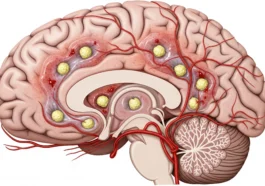

in BrainsBrain Angiography: Understanding Life-Saving Diagnostic Procedure

When doctors need the clearest possible look inside the brain, brain angiography is their superhero tool. It lets them spot dangerous problems early—like aneurysms or blocked vessels—before they turn into something serious. If you’ve ever wondered how doctors can actually see blood moving inside your brain, this is how. What Is Brain Angiography? Think of […] More